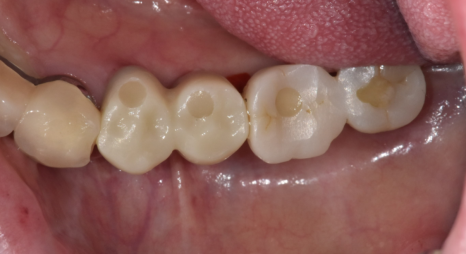

▼완성 사진▼

오늘은 명일동 치과에서

임플란트 치료 기간과 관련한 이야기를 해드렸습니다.

사람마다 치료 기간은 다릅니다.

그렇지만 중요한 것은

늦게 치료하러 오실 수록

치료기간은 길어진다는 것